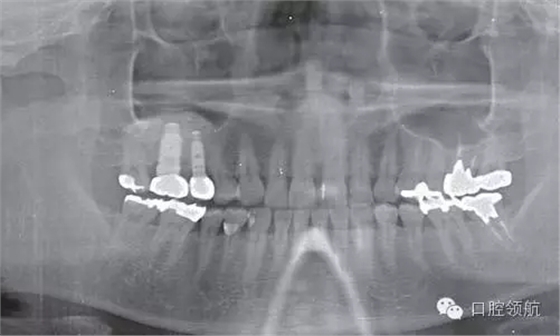

術(shù)后8個月未見異常(圖8),并完成( 左上第五顆牙) 的上部修復(fù)(圖9)。

圖8 術(shù)后8個月的牙片。兩顆種植體愈合良好。

圖9 術(shù)后8個月戴入上部修復(fù)后的曲面斷層片。